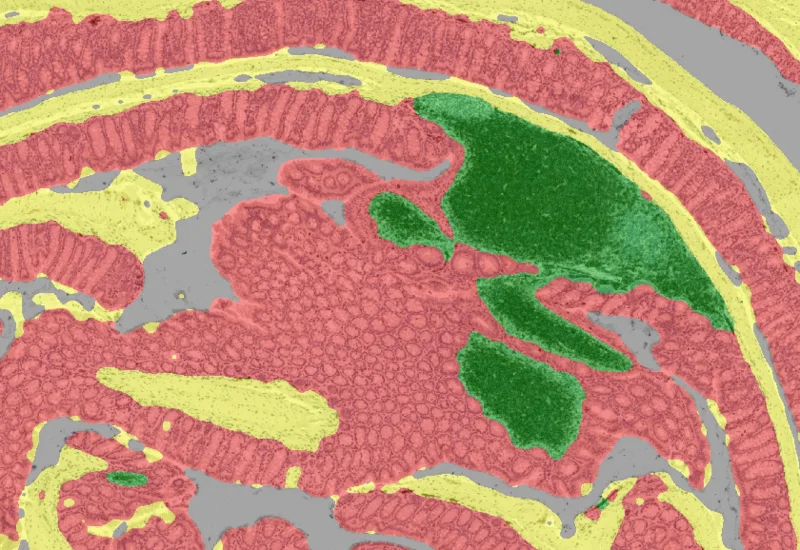

The IF Swiss Roll App segments tissue into subclasses (e.g., mucosa, follicles, connective tissue), detects nuclei, and identifies phenotypes via IF stains.

The IF Swiss Roll App allows for detection of the swiss roll, and the segmentation into different subclasses (mucosa, immune cell follicles, connective tissue, background). Further it detects nuclei and identifies phenotypes based on specific IF stains. The App outputs area (µm2) of detected tissues/tissue classes, count of total cells as well as in each detected area. Count and % of specific phenotype detected in total as well as in the tissue classes.

Tissue classification